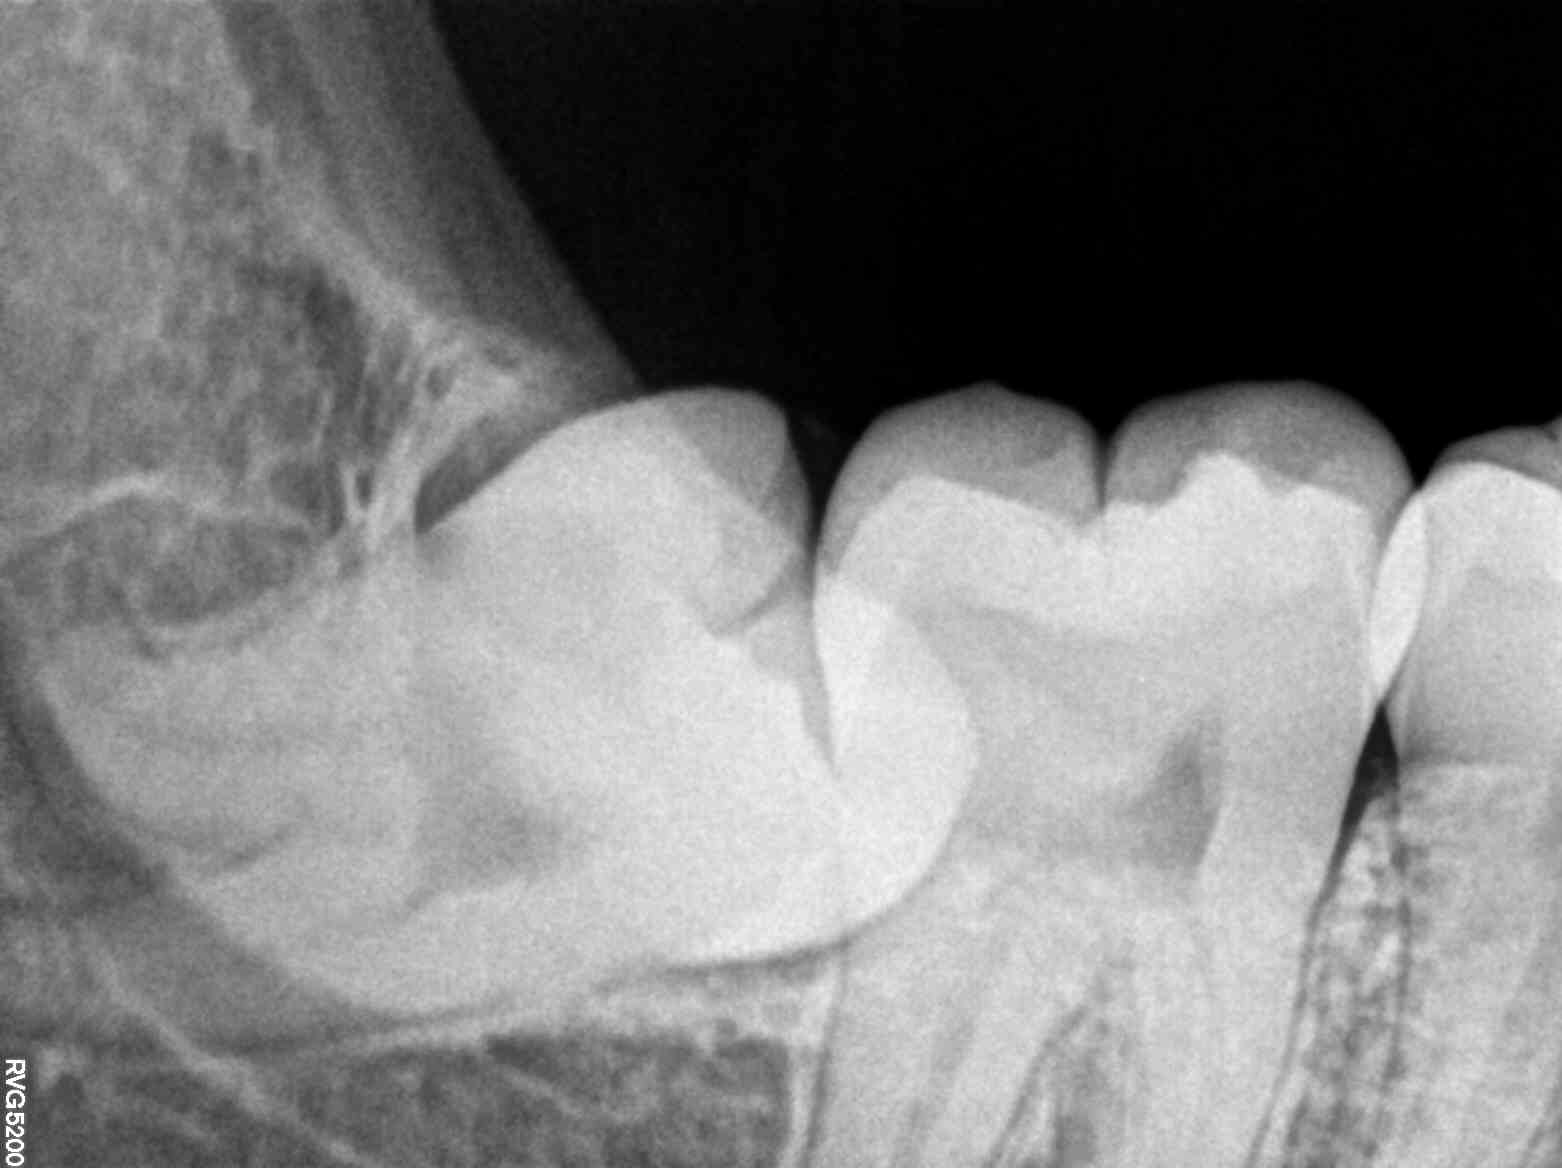

Dental X-rays are not just about viewing teeth; they are a gateway to understanding the hidden intricacies of oral health. When Meera finally visited her local dental clinic, she was apprehensive about what the dentist might find. Her dentist, Dr. Rajiv, recommended a comprehensive dental X-ray to get a full picture of what was happening beneath the surface.

The results were revealing. The X-ray showed early signs of gum disease and a cavity that, if left untreated, could have led to a tooth extraction. Dr. Rajiv explained the importance of catching these issues early, highlighting how the X-ray had saved Meera from potential pain and more invasive procedures down the line. For Meera, the X-ray provided clarity and a path forward, turning her anxiety into empowerment.

Dr. Rajiv set a treatment plan in motion, focusing first on treating the cavity and then addressing the early-stage gum disease. With the help of regular cleanings, a prescribed oral care routine, and periodic check-ups, Meera was back on track. Her story is a testament to the power of modern dental X-rays in transforming oral health journeys.